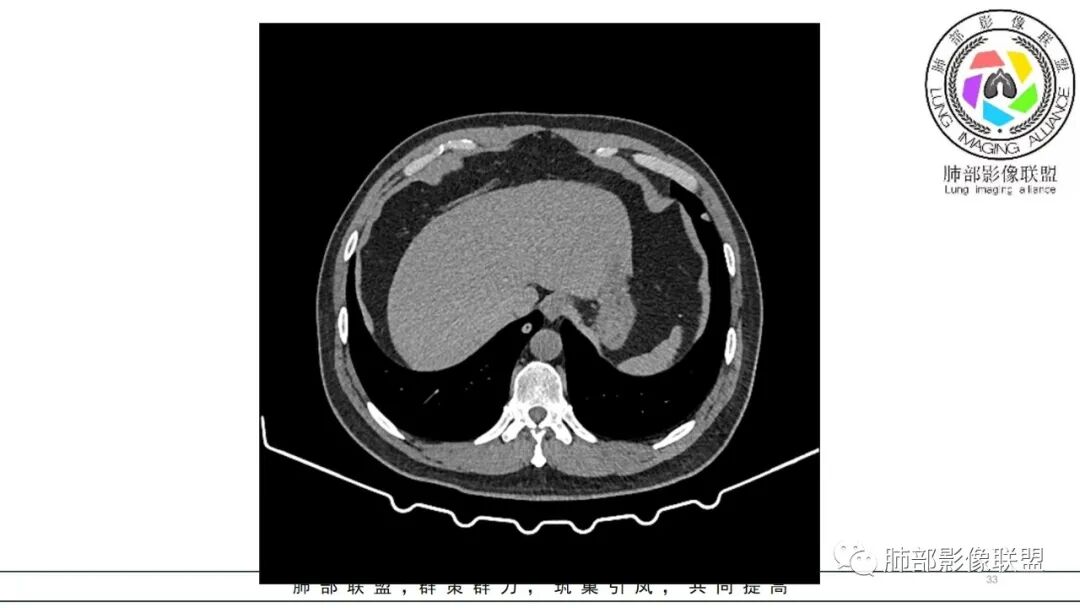

中年男性,咳嗽咳痰低热三天。右肺中叶、下叶条片状高密度影,局部边缘有晕,可见卫星灶。双肺另见多发小结节。考虑炎性肉芽肿,PC,鉴别GPA

中年男性,咳嗽咳痰伴发热3天,有鼻窦炎、 中耳炎病史,血沉、 CRP 增高,中性粒稍高。

双肺多发实性小结节,边清,多位于胸膜下。右肺中叶不规则实变影,沿支气管血管束走行,似有跨叶。